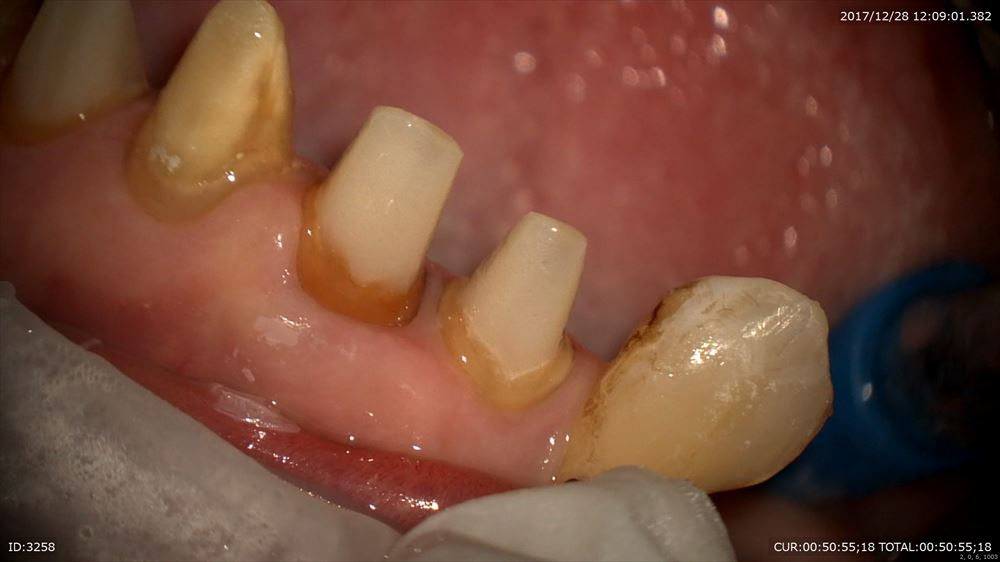

次は精密根管治療

前回から根管治療開始。1回の治療で「今まで腫れていたのが嘘みたい!!」とお褒めのお言葉を頂きました。歯は原因が取れれば治癒の方向へ向かいますとお話ししました。私も嬉しい!!根管治療は回数ではありません。当院では平均3回で終了しています。回数が増えるほど、しかも、もしその際ラバーダムなど無菌的処置をしていなければ感染する機会が増え一向に治りません。だから当院は短期集中。

綺麗になりました。

術前と術後

もちろん無痛です。